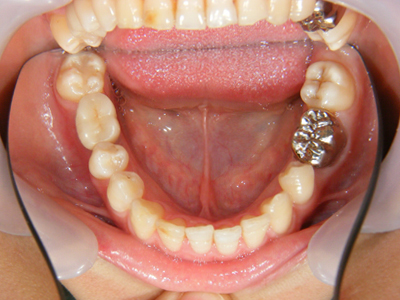

14. インプラント歯冠セット時下顎面観

右下6番部インプラントにセラミック冠を装着(ほとんどの症例では仮着)した下顎写真です。

15. インプラント歯冠セット時右側面観

右下6番部インプラントにセラミック冠を仮着したところです。何とか歯頚部の連続性が保てました。又歯冠乳頭も少し温存できました。キャンセルが多く苦労しましたが、今後は確実に定期健診を受けて下さらないと保障できませんよ。何かあれば、いつでも相談してください。